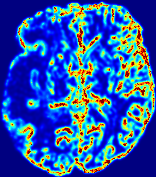

LesionRefer to captionRefer to captionRefer to captionRefer to captionRefer to captionRefer to caption𝐕rgbsubscript𝐕𝑟𝑔𝑏{\bf{V}}_{rgb}Refer to captionRefer to captionRefer to captionRefer to captionRefer to captionRefer to caption𝐕2subscriptnorm𝐕2{\|\bf{V}}\|_{2}Refer to captionRefer to captionRefer to captionRefer to captionRefer to captionRefer to captionRefer to caption3.53.53.52.82.82.82.12.12.11.41.41.40.70.70.70.00.00.0(mm/s)𝑚𝑚𝑠(mm/s)D𝐷DRefer to captionRefer to captionRefer to captionRefer to captionRefer to captionRefer to captionRefer to caption0.0200.0200.0200.0160.0160.0160.0120.0120.0120.0080.0080.0080.0040.0040.0040.0000.0000.000(mm2/s)𝑚superscript𝑚2𝑠(mm^{2}/s)Slice #1Slice #2Slice #3Slice #4Slice #5Slice #6

Figure 3: PIANO feature maps for one stroke patient, where the lesion is located in the left hemisphere. Top row: segmented stroke lesion region (white) on different slices, obtained from ISLES 2017. The corresponding slices for the PIANO feature maps are shown in the following rows.

For a better insight into an estimated velocity field 𝐕𝐕{\bf{V}} and diffusion field 𝐃𝐃{\bf{D}}, we compute the following maps: (1) 𝐕rgbsubscript𝐕𝑟𝑔𝑏{\bf{V}}_{rgb}: Color-coded orientation map of 𝐕=(Vx,Vy,Vz)T𝐕superscriptsuperscript𝑉𝑥superscript𝑉𝑦superscript𝑉𝑧𝑇{\bf{V}}=(V^{x},V^{y},V^{z})^{T}, obtained by normalizing 𝐕𝐕{\bf{V}} to unit length and mapping its 3 components to red, green, blue respectively; (2) 𝐕2subscriptnorm𝐕2\|{\bf{V}}\|_{2}: 222 norm of 𝐕𝐕{\bf{V}}; (3) D𝐷D: scalar field in Eq. 5.

Fig. 3 and Fig. 4 show the PIANO feature maps estimated from two ISLES 2017 patients: all are highly consistent with the lesion in both cases. Details of the blood flow trajectories are revealed in 𝐕rgbsubscript𝐕𝑟𝑔𝑏{\bf{V}}_{rgb} by the ridged patterns and the sharp changes of colors in the unaffected (right) hemisphere, while the flat patterns appearing within the lesion provide little directional information about the velocity and indicate low velocity magnitudes. Velocity magnitudes are more directly visualized via 𝐕2subscriptnorm𝐕2\|{\bf{V}}\|_{2}, from which one can easily locate the lesion where 𝐕2subscriptnorm𝐕2\|{\bf{V}}\|_{2} is low. D𝐷D also indicates lower diffusion values in the lesion, though with less contrast potentially due to the fact that it captures the accumulated effect of CA diffusion at the voxel-level.